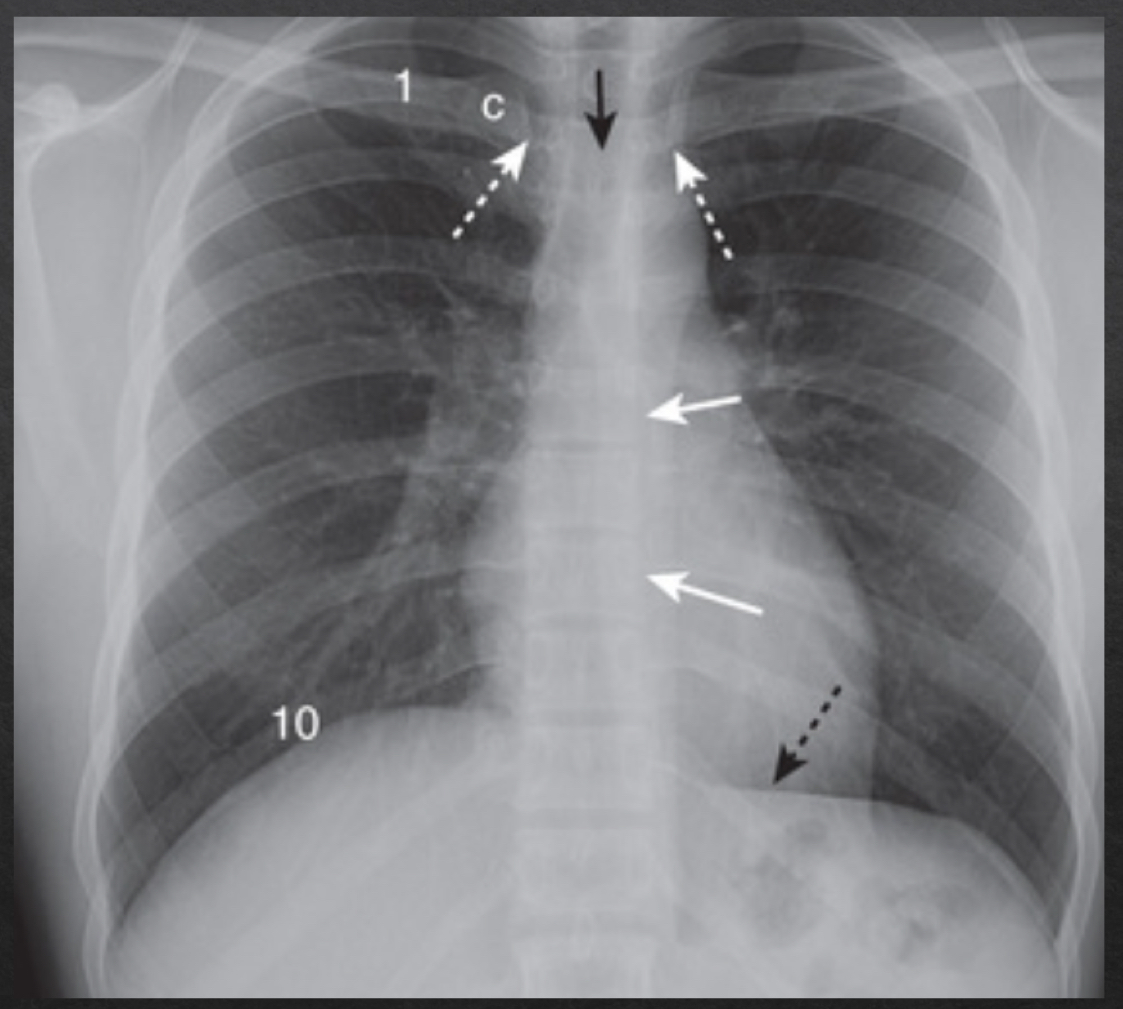

rotation

adequate rotation: spinous processes are equidistant btwn the medial ends of the clavicle

severe rotation findings

trachea appears shifted from midline (black arrow)

left lung appears much larger, right lung appears smaller

heart contour appears changed

left hemidiaphragm appears raised (white arrow)